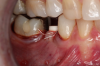

Fig 11. Preoperative healed sites.

Figure 11

Fig 12. Ceramic implants placed and sutured.

Figure 12

Fig 13. Lateral view after placement.

Figure 13

Figure 10 through Figure 13 show the preoperative x-ray and the sequence of beginning with healed sites through the surgical placement of the implants. The implants were protected by an Essix-style wound-protection removable retainer for approximately 12 weeks. After the integration phase, the implants and the natural dentition were prepared using traditional crown-and-bridge high-speed diamond and zirconia cutting burs to remove decay and existing restorative materials, to complete and refine the natural-tooth structures to receive full-crown coverage, and to prepare and refine gingival margins of the zirconia implants where needed.